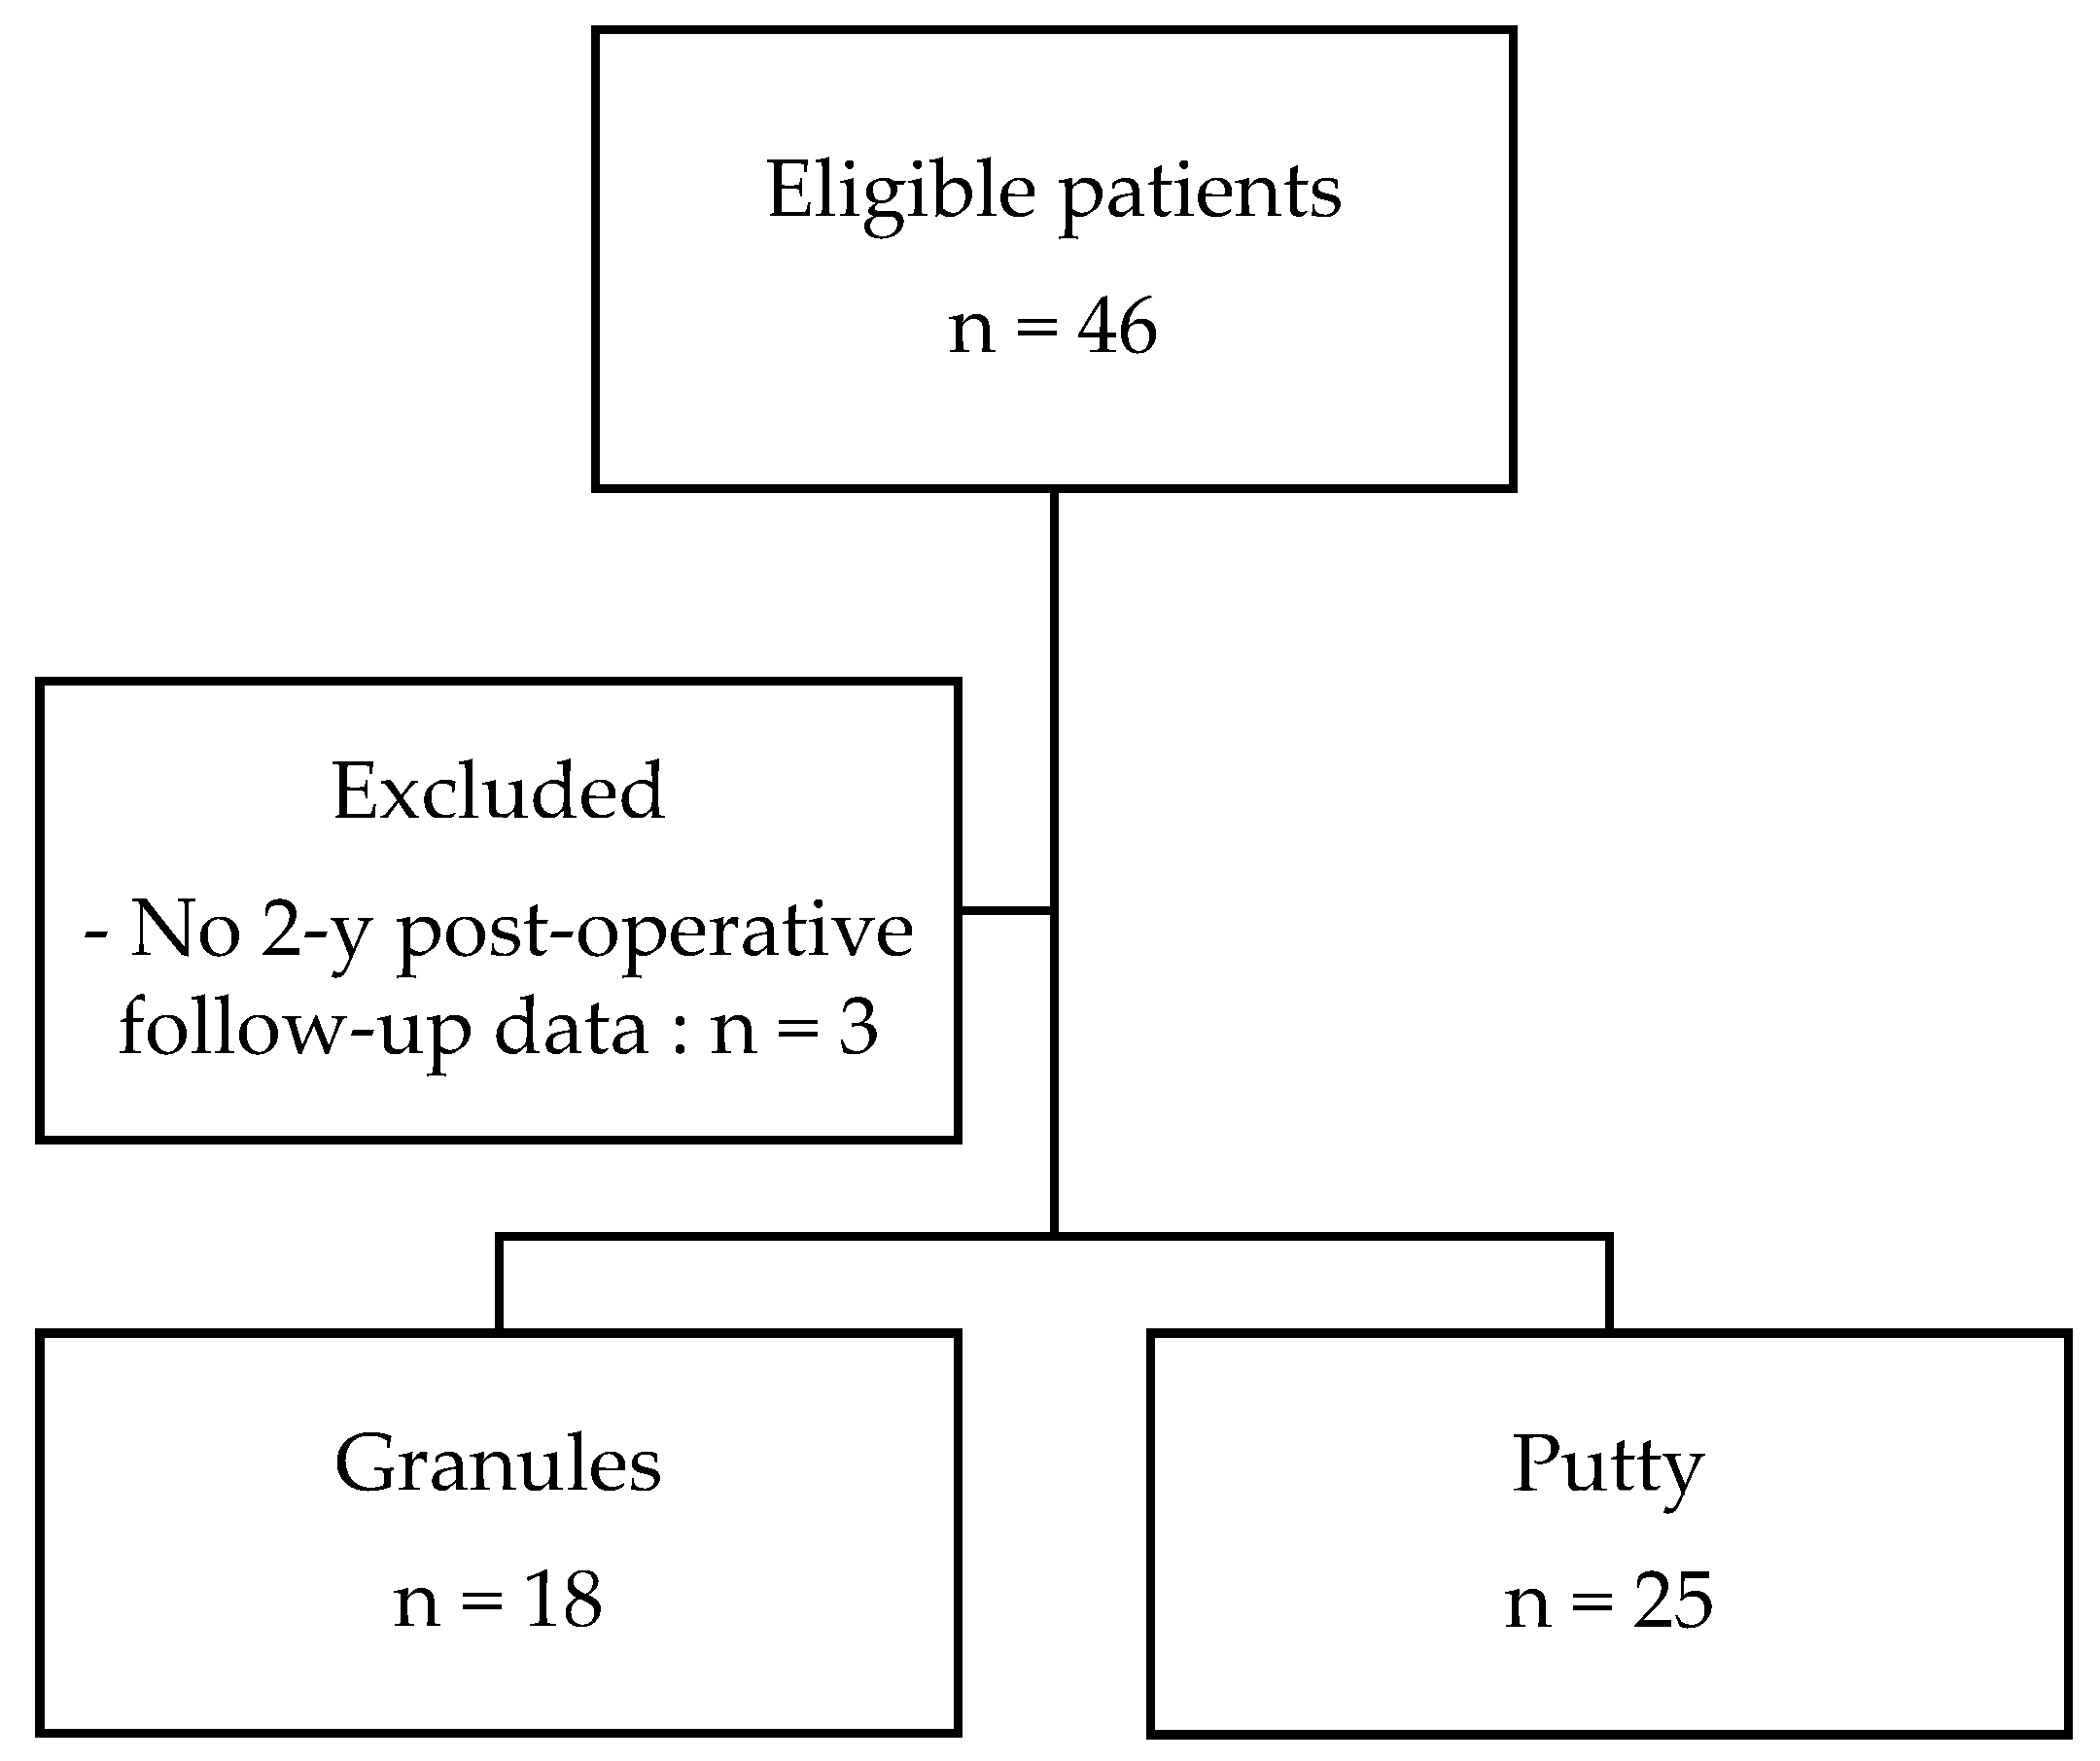

2.1. Patient Selection

3.1. Patient Selection and Demographic Data